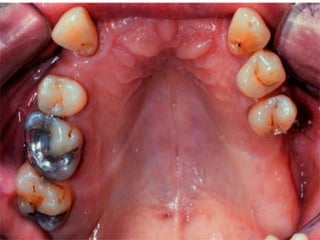

Class III Unilateral edentulousarea with natural teeth both anterior and posterior to it.